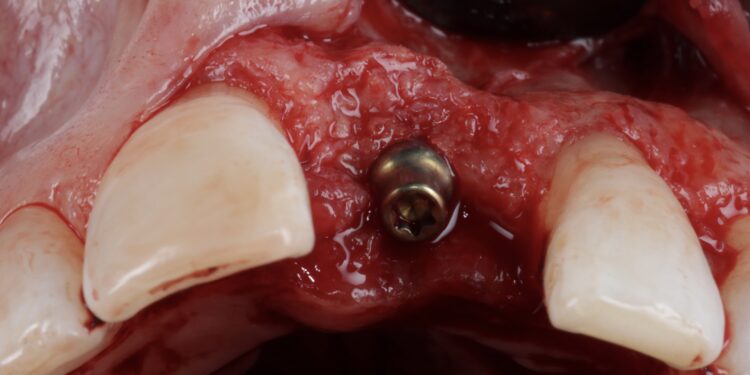

Once the orthodontic treatment was completed, the site was re-evaluated, and it was clear to see that the gingival zenith had significantly improved. The patient was advised that without re-contouring the mesial aspect of the contralateral central incisor there would be a midline black triangle. She rejected the option of composite addition to alter the triangular shape of the UR1 and thus we proceeded to complete the treatment without this. The implant was placed with simultaneous buccal GBR & connective tissue graft following a transmucosal approach. Following a healing period of 4 months, the restorative treatment was initiated with a temporary crown to develop the emergence profile. Once the gingival zeniths had been matched, the patient was delivered a permanent screw retained crown.